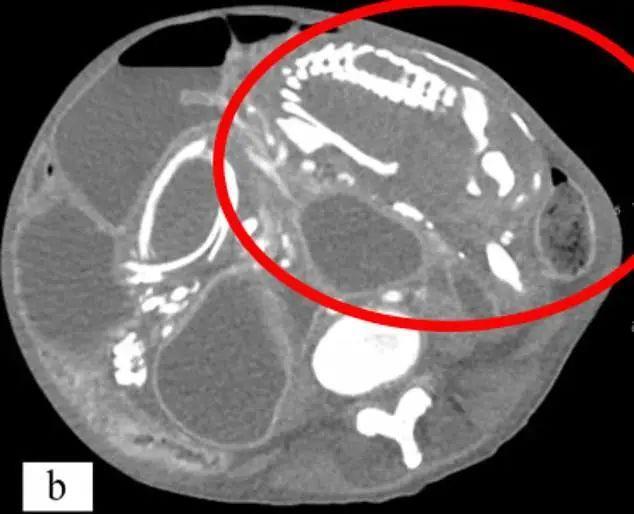

而CT检查结果显示,这些症状都是多年前留在体内的那只“死胎”造成的。

因为胎儿去世后一直留在腹部,免疫系统认为这只死胎对身体构成了威胁,对它发起猛烈攻击,于是,含钙的沉积物沉积在胎儿身上,逐渐将它包裹在钙化壳中,变成一块形似木乃伊的“石头”,也就是医学文献中记载的罕见出现的“石胎”。

但根据CT显示,这位刚果妇女体内的石胎足足有“15*20cm”大小,在九年时间里不断压迫她的肠道,肠道阻塞使她时常腹部绞痛、剧烈呕吐、食欲不振,且无法吸收重要的营养,因此日渐消瘦,憔悴不堪…